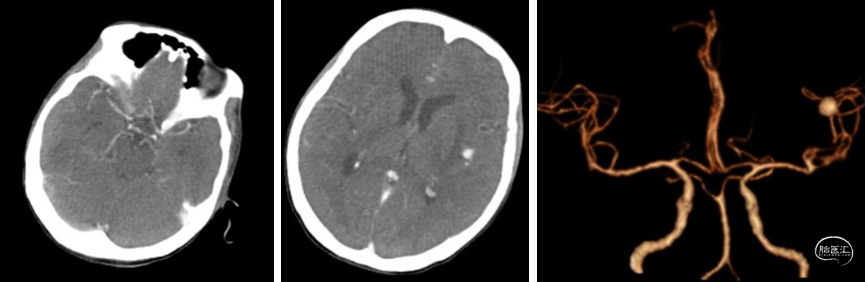

2023年11月23日来我院急诊完善头CTA(未见动脉瘤)、胸腹CT后,11/24急诊全麻下行“二尖瓣成形、三尖瓣成形、心外膜临时起搏电极植入术”;术后返外科ICU,恢复顺利,11/28返心外病房,11/29患者出现反应迟钝、言语减少,急查头CT见颅内多发高密度灶,保守治疗。11/30复查头CT较前变化不明显,之后患者颅内病情平稳,12/4转入感染科继续抗感染治疗。12/10 20点排便后,突发意识障碍,急查头CT提示颅内高密度较前明显扩大,出血可能。急诊抢救、插管后,查头颈CTA提示颅内多发动脉瘤、多发出血、大脑镰下疝。

颅内影像